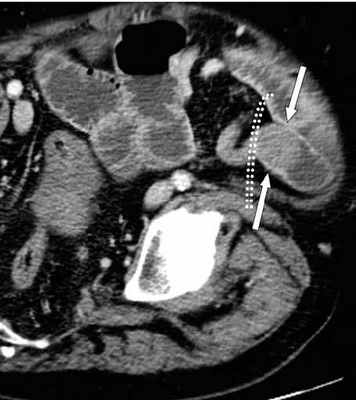

Декомпенсированная форма

Определяются все признаки, описанные при простой форме, дополнительно появляются патологические изменения в брюшной полости:

-расширенные петли тонкой кишки проксимальнее транзиторной зоны (зоны обструкции);

-спавшиеся петли кишечника дистальнее уровня обструкции;

-нормальные не утолщённые стенки кишечника с гомогенным одинаковым контрастным усилением;

-свободная жидкость между расширенными петлями кишечника, зачастую в виде пикантной детали женского туалета-трусиков танга, поэтому в многих источниках описывается как признак "танга" (tanga sign);

-свободная жидкость в брыжеечных карманах;

-свободная жидкость в брюшной полости.

Примеры скопления жидкости между петлями кишечника (танга) и в карманах брыжейки при декомпенсированной форме.